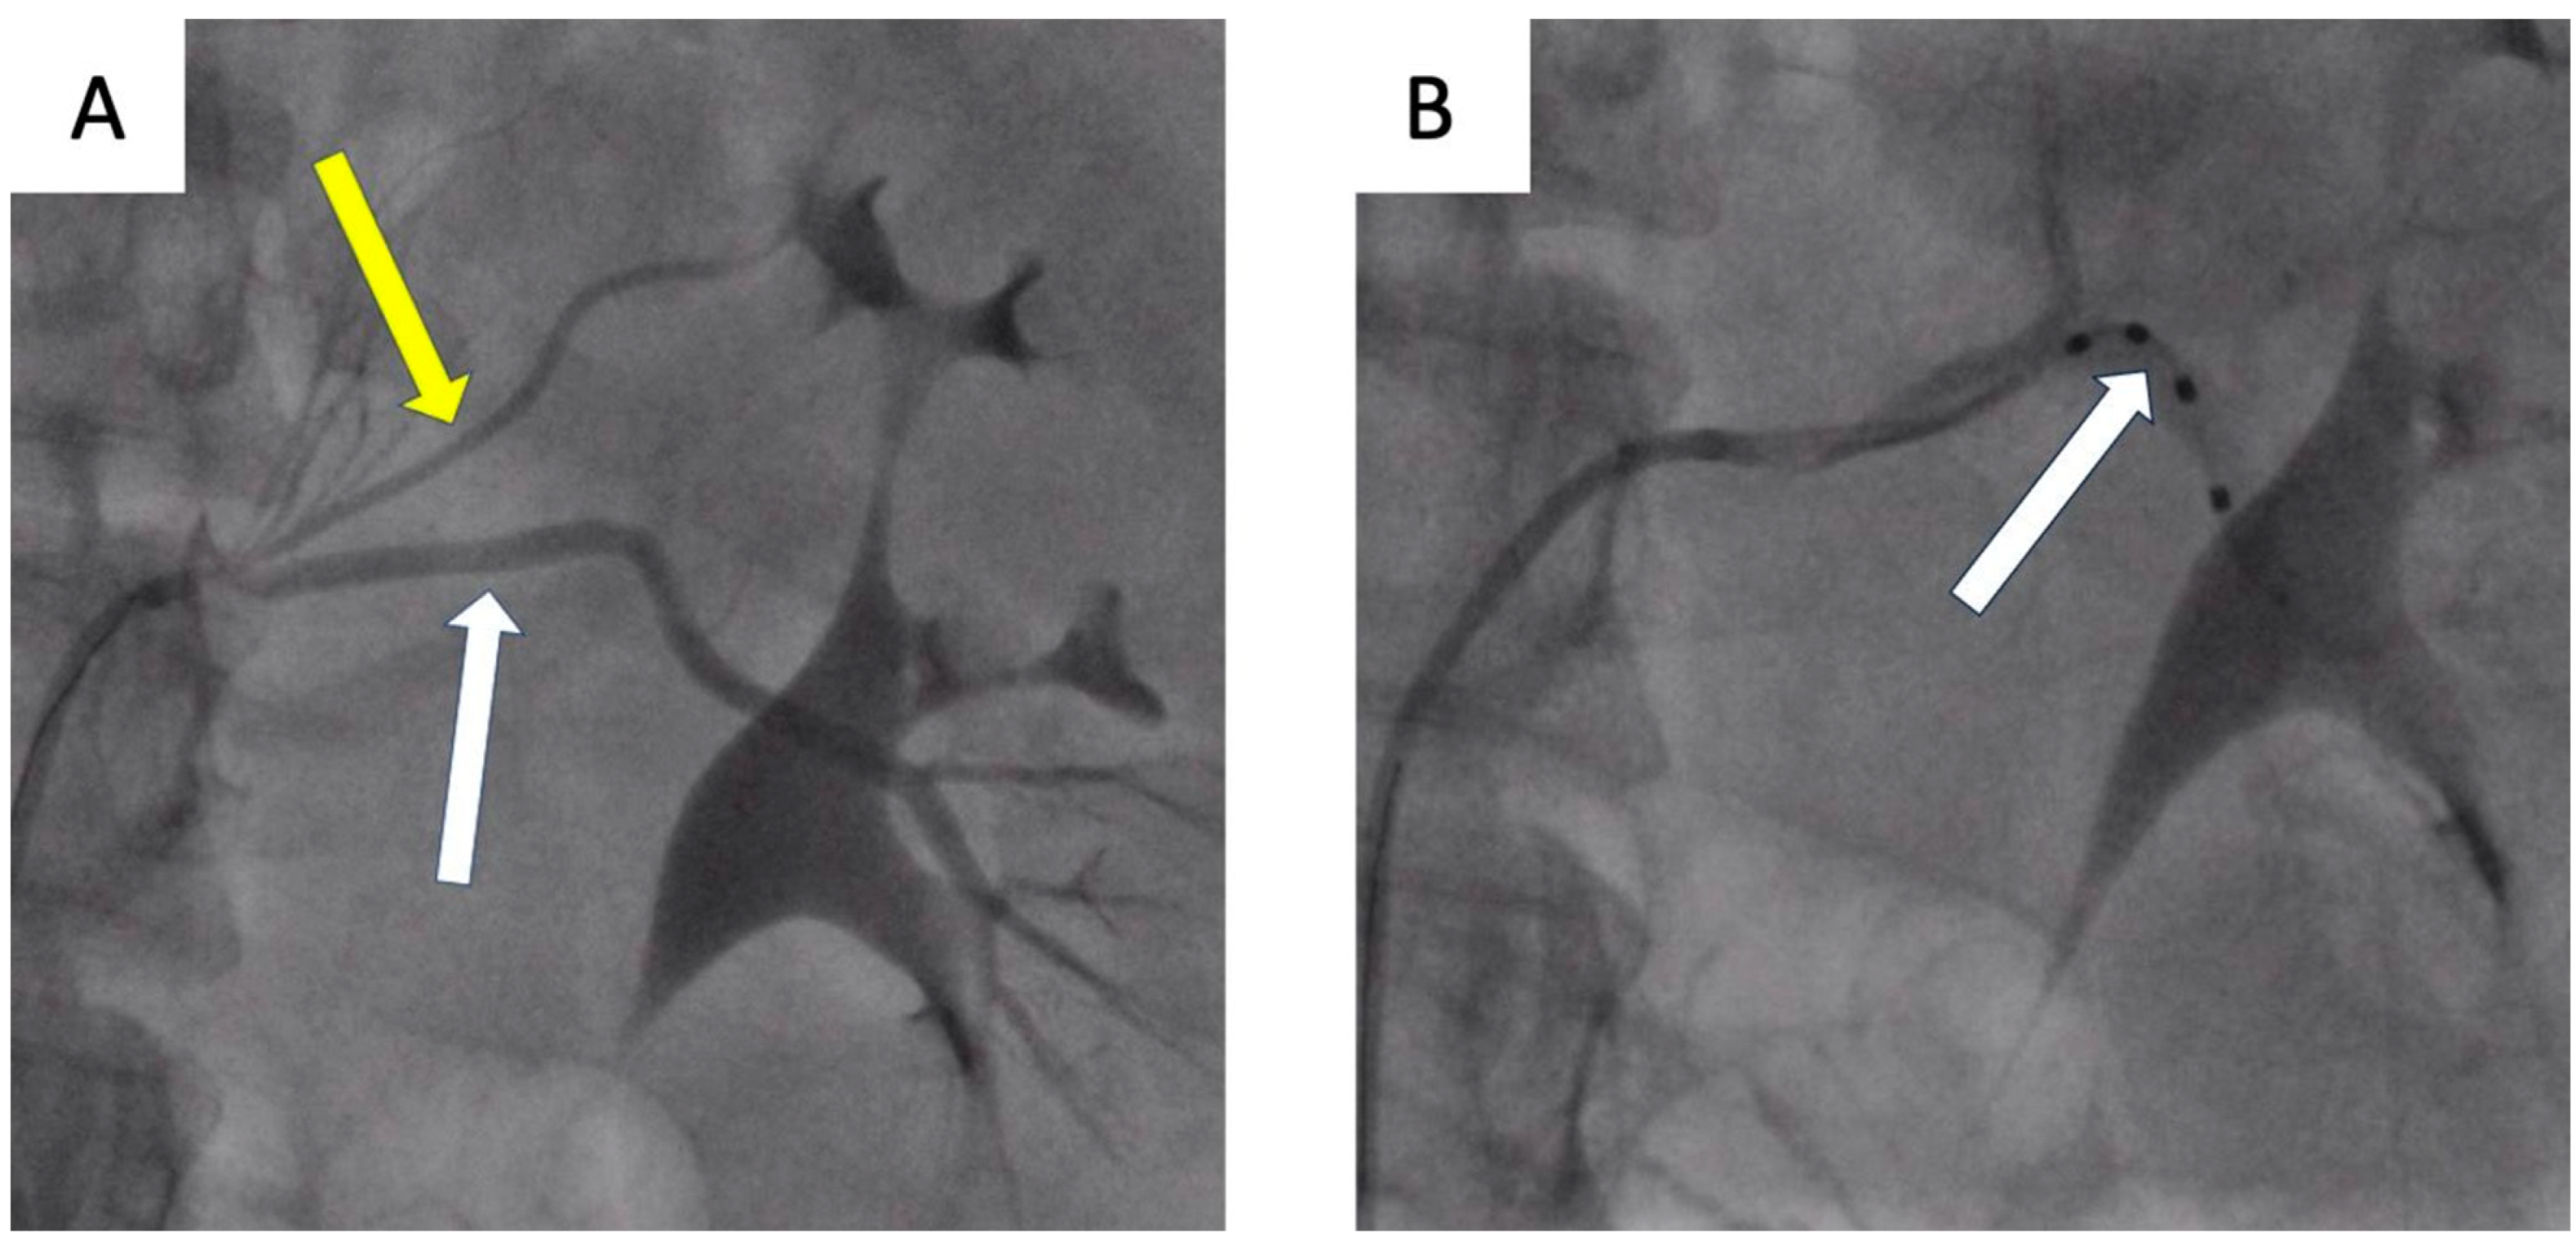

- Tokarek, T.; Rajtar-Salwa, R.; Rzeszutko, Ł.; Bartuś, S. Long-term benefit of redo sympathetic renal denervation in a patient with resistant hypertension. Postep. Kardiol. Inter. 2021, 17, 239–241. [Google Scholar] [CrossRef] [PubMed]

- Atas, H.; Durmus, E.; Sunbul, M.; Mutlu, B. Successful accessory renal artery denervation in a patient with resistant hypertension. Heart Views 2014, 15, 19–21. [Google Scholar] [PubMed]

| de Leon-Martinez, Enrique Ponce et al. [45] | 55-yo man | Proximal bifurcation in the left RA and right ARA | RDN, RF ablation catheter (Symplicity Medtronic) | Five to two drugs | −29/9 after one month, −50/20 after two moths |